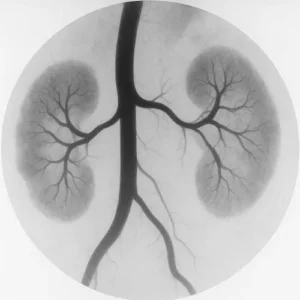

Iodinated Contrast and Acute Kidney Injury

Iodinated contrast media are indispensable in CT angiography, CT urography, and many interventional radiology procedures. Historically, “contrast-induced nephropathy” (CIN) was the term used to describe an acute rise in serum creatinine after exposure. Today, that terminology has shifted toward “contrast-associated acute kidney injury” (CA-AKI), reflecting the recognition that not all kidney injury temporally related to contrast exposure is caused by the contrast itself.

Modern studies, particularly those employing matched control groups, have shown that in many cases—especially when baseline estimated GFR (eGFR) is above 30 mL/min/1.73 m²—the incidence of true contrast-induced injury is far lower than once feared. However, risk is not eliminated. Patients with advanced CKD, active volume depletion, concurrent nephrotoxins, or hemodynamic instability remain more vulnerable. In these individuals, contrast risk in CKD still carries meaningful clinical weight.

When iodinated contrast is necessary in higher-risk patients, strategies such as isotonic volume expansion before and after the procedure, minimizing contrast dose, and avoiding unnecessary repeat exposures can help mitigate harm. Understanding contrast risk in CKD also ensures that preventive measures are applied without unnecessary delay to critical imaging.